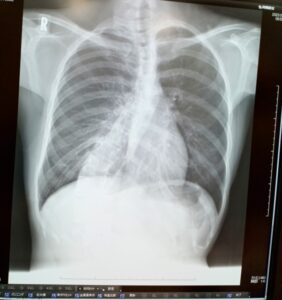

側弯症は、原因が不明で治癒が困難とされる「特発性側弯症」と、骨盤の歪みに起因し骨格矯正で改善が見込める「機能性側弯症」に大別されます。当院ではこれまで、1例の特発性側弯症と数例の機能性側弯症に対応してまいりました。

背骨の形状が円筒形になり、脊柱の生理的な湾曲を構成するための角度差がなくなっている状態と考えられます。骨格に歪む要素が見当たらないにもかかわらず、全体的に歪みが生じているのが特徴です。 - 機能性側弯症

骨盤の歪みが明確に確認され、それが原因となって脊柱の歪みが起きている状態です。

しかし、あるお客様は初診時に側弯症の特徴が見られたにもかかわらず、他の患者様とは異なり、症状を何とかしたいという「非常に強い熱意」を持たれていました。この積極的な姿勢に注目し、施術を進めたところ、驚くべき結果が得られました。

その結果、初回から施術効果の蓄積が見られ、着実に改善していったのです。これは驚異的な事例であり、側弯症の改善可能性を高めるものとなりました。